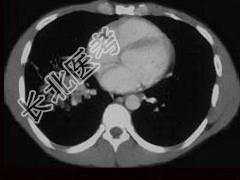

- 单项选择题男,42岁, 高热,寒战, 咳嗽,胸痛1周左右, CT检查如图,选择最可能的诊断 ( )

A、肺结核

B、肺癌

C、肺囊肿

D、肺脓肿

E、肺转移瘤